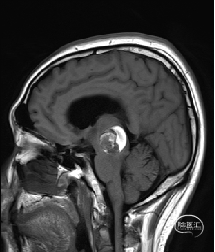

术前DTI检查

根据MRI及DTI显示,只有在丘脑与上丘之间的点(dot)进入病变才可能在切除病变时最大程度保护神经功能,由于上述原因,该“点”在术中显露极其困难,虽有导航指引,电生理监测的条件下,对术者的耐心、技术、经验及体能依然是极大的挑战;

术前详细的磁共振检查,包括平扫增强,SWI及DTI,可以规划出手术最适宜的路径及切入点;